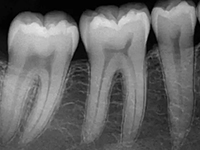

全面口腔检查,并根据龋齿的数量、疗位、龋病的病变程度制定最佳的补牙修复方案。

早龋,一次消毒即可进行补牙,中龋或深龋,则需m三至五次,如果涉及到牙神经则需根管治疗。